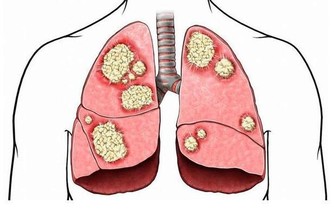

肝臟是人體主要以代謝功能為主的一個器官,也是人體最大的器官。每年全球新患肝癌人數為74.8萬人,有50%發生在中國,除此以外,預計,肝炎、脂肪肝、肝癌、酒精肝等慢性肝臟疾病,我國2020年總數將達4.47億人,對人的傷害不容小覷,早發現早治療極為重要。

肝臟是一個無聲的器官,很多人發現肝癌的時候,已經是晚期,治愈率很低,防大於治,養肝重在日常